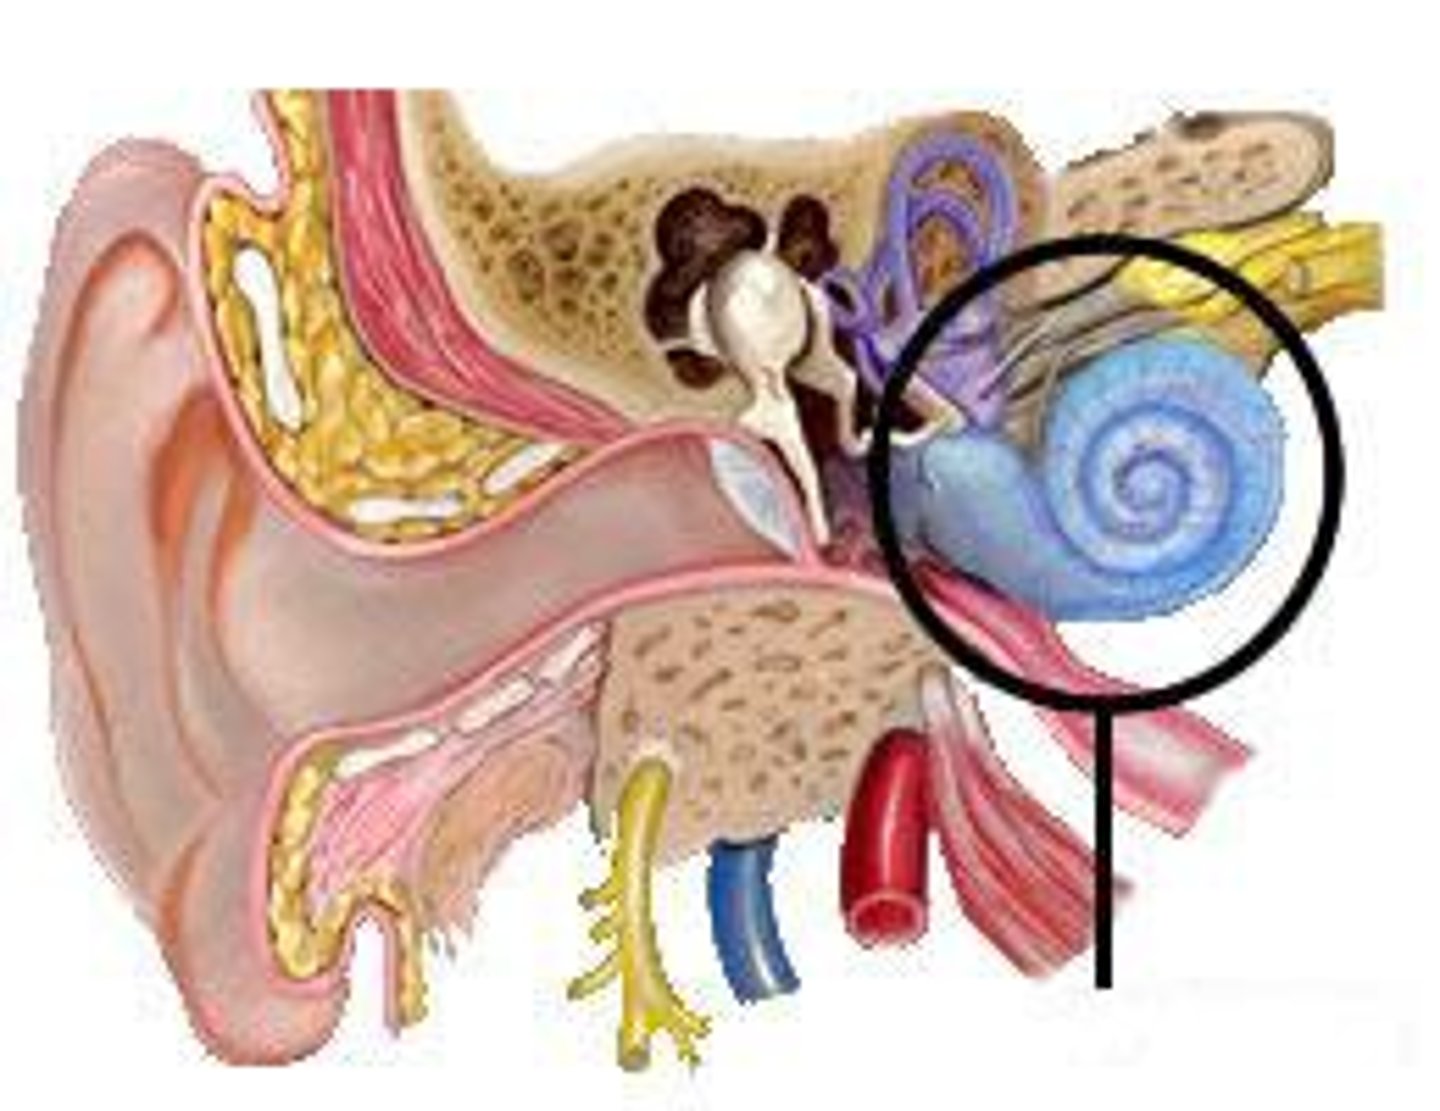

cochlea

cochlear nerve

labyrinth (osseous + membranous)

(general structure, ignore arrow)

oval window

round window

scala tympani

scala vestibuli

semicircular canals

spiral organ (of corti)

section of cochlea

vestibular nerve

vestibule

vestibulocochlear nerve